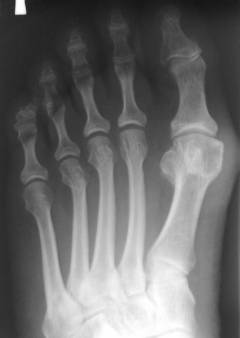

Стопа состоит из 26 костей, которые делятся на три группы в зависимости от расположения и функций.

Скелет стопы включает:

- Плюсна. Состоит из 5 коротких трубчатых костей, соединяющих фаланги пальцев с предплюсной. Суставные поверхности на обоих концах этих костей увеличивают диапазон движений пальцев.

- Фаланги пальцев. Включают 14 костей (по 2 для первого пальца и по 3 для остальных четырех), образующих подвижный скелет пальцев, которые помогают поддерживать равновесие и выполняют мелкие движения.

Костный скелет стопы состоит из 26 костей, соединенных малоподвижными суставами. Эти кости испытывают значительные нагрузки, поддерживая вес тела и поглощая энергию при движении.

Плюсневые кости. Пять коротких трубчатых костей с изгибом, направленным вверх, что способствует формированию свода стопы. Каждая имеет две суставные поверхности и бугристости для прикрепления мышц и сухожилий.

Фаланги пальцев. По количеству и расположению аналогичны пальцам руки. Первый палец состоит из двух фаланг, остальные — из трех. Фаланги пальцев стопы короче и толще, что связано с их функциональной нагрузкой.

Основным методом диагностики является рентгенологическое исследование, позволяющее определить тип и расположение перелома. Перед рентгеном врач проводит клиническое обследование.

Рентгеновские лучи позволяют выявить переломы благодаря различной степени их поглощения костной и мягкой тканью.

Из-за большого количества мелких костей диагностика переломов в этой области требует глубоких знаний анатомии.